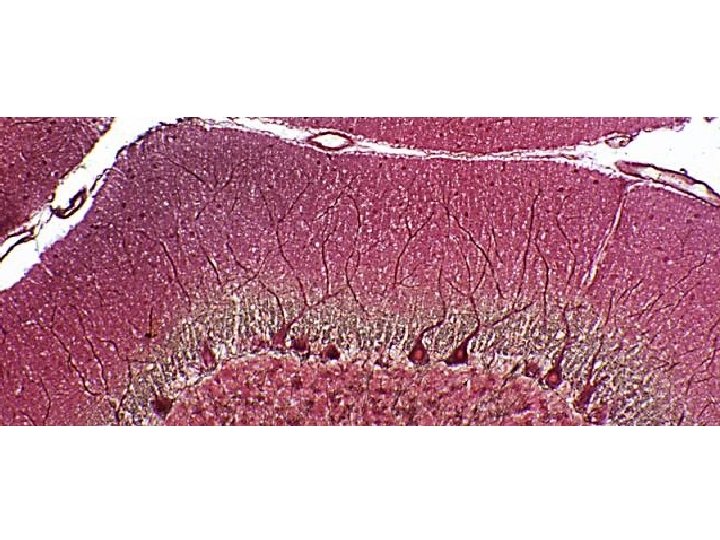

Capa de las células de Purkinje Célula de Purkinje Fibra trepadora Inhibición Célula nuclear profunda Excitación Aferencia (oliva inferior) Eferencia Capa Granulosa Células Granulares Núcleos profundos Fibra Musgosa Aferencias (El resto de aferentes) Corteza Capa Molecular

• El Cerebelo emite señales de encendido-apagado y Capa apagado-encendido Célula de Purkinje - Fibra trepadora Célula nuclear profunda Capa de las células de Purkinje Inhibición + Excitación + Aferencia (oliva inferior) Eferencia Capa Granulosa Células Granulares Núcleos profundos Fibra Musgosa Aferencias (El resto de aferentes) Corteza Molecular

LAS CÉLULAS DE PURKINJE “APRENDEN” A CORREGIR LOS ERRORES MOTORES: IMPORTANCIA DE LAS FIBRAS TREPADORAS